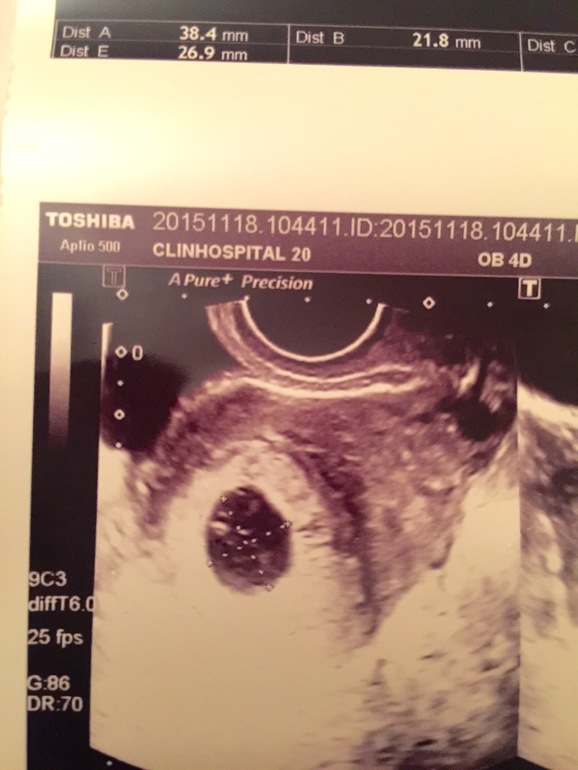

УЗИ снимок!!!

а ктр размеры указаны?мне в 6 делали на снимке пя а внутри прям видно был "головастик"..

Да плодное яйцо, не знаю в двух клиниках делала , это первая но я сомневаюсь в компетентности врача , так как она научила говорить про мои кишки, причём тут мои кишки, докаталась, прошу прощение типо у вас понос!! Я говорю у меня нет поноса, она мне говорит нет есть... Короче напугала меня... Я в замешательстве

))) так она вам через живот смотрела? Вообще просто плодное яйцо, мне кажется , если размеры верные, то 7 недель нет еще... Подождите дней 10 и повторите узи... Пугаться пока не надо ;) очень рано...